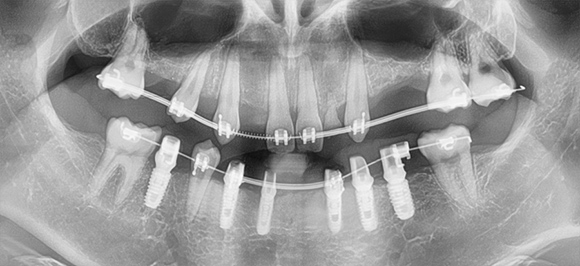

상악동 임플란트는 치과치료 중 난이도 높은 임플란트

윗 턱뼈와 코가 연결된 빈 공간을 확보하여 활용

윗니(좌·우 양쪽 치아) 임플란트 진행 시, 뼈이식과 함께 진행